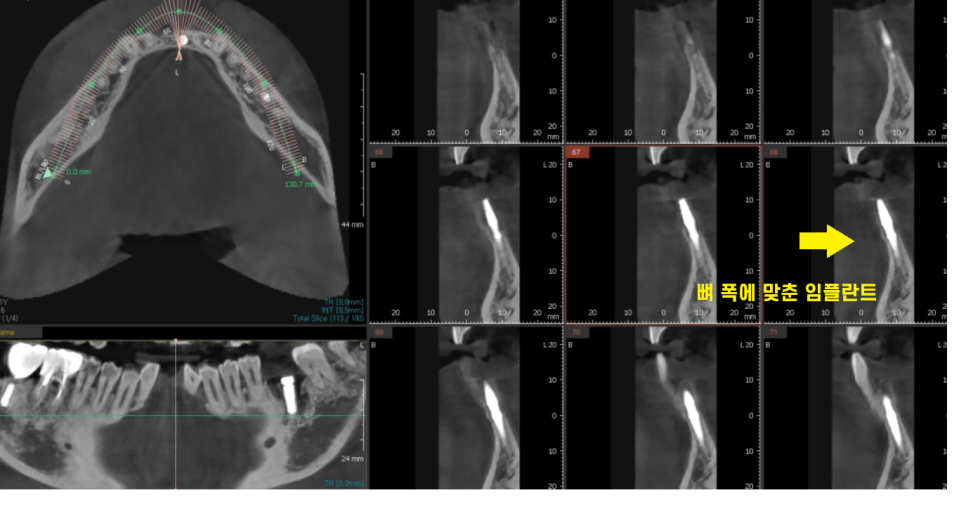

23.06.16

ct를 보시면 임플란트가 뼈 폭에

기가막히게 딱 ! 맞아 떨어집니다!

두개의 임플란트를 못심을정도로

뼈가 없었지만

일체형 임플란트를 통해

아래 앞니 임플란트 해결했습니다!!